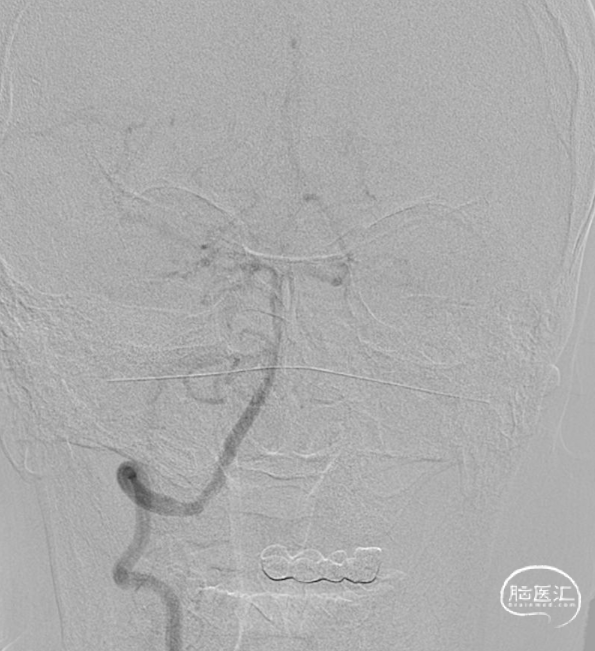

术前影像

脑血管造影(主动脉弓造影及后循环)

右侧颈动脉造影

左侧颈动脉造影

左侧颈内动脉重建(左侧狭窄及扩张较右侧更甚)

手术过程

经Cat5完全释放支架后,拉推送杆后支架近端打开,后将Cat5跟进血流导向装置内尝试“按摩”,支架整体贴壁不够理想。

Cat5通过后海绵窦段狭窄即较前改善

Cat5提供稳定通路,引入3.5mm×10mmHiryu球囊扩张由远端及近端扩张狭窄段及支架贴壁欠佳处

造影示狭窄及贴壁较前进一步改善

导丝成袢,继续“按摩”改善贴壁

“按摩”后再次造影,C2段狭窄仍较明显且贴壁欠佳

再次引入球囊扩张近端

扩张后再次复查造影示支架打开及贴壁较前明显改善

标准正侧位造影未见远端血管栓塞

稀释造影提示支架贴壁可,狭窄改善